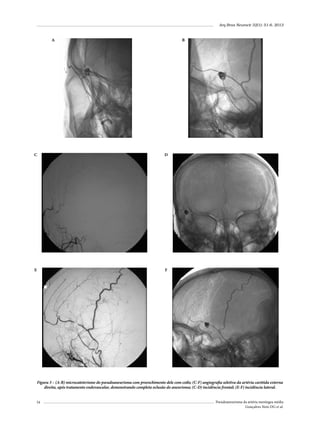

endovascular treatment of two cases and review of the

literature. Neuroradiology. 2012;54(10):1133-6.

10.

Wang CH, Lee HC, Cho DY. Traumatic pseudoaneurysm of

the middle meningeal artery: possible indicators for early

diagnosis in the computed tomography era. Surg Neurol.